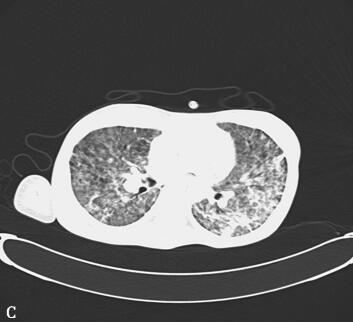

第二阶段(入院后第7~26天):二尖瓣置换术后患者心功能明显改善,多次复查心脏超声均提示心脏舒张及收缩功能未见明显异常,瓣膜功能良好。但患者感染难以控制,考虑感染源:①肺部感染:无法脱离ECMO,胸片提示双肺渗出影(图1),多次痰培养结果均提示鲍曼不动杆菌(MDR);②血源性感染:多次外周血及导管血培养提示洋葱伯克霍尔德菌;③感染性心内膜炎:考虑患者存在急性感染性心内膜炎,瓣膜赘生物形成,多为革兰阳性杆菌感染,但赘生物培养却未见细菌生长。鉴于以上感染相关证据,调整抗感染治疗方案为达托霉素和美罗培南联合左氧氟沙星,并加强气道管理,入院24天后病情明显好转,感染得到控制,逐渐增加呼吸机支持条件,并降低ECMO辅助条件,患者氧合及循环情况均未见恶化,复查胸片渗出较前吸收(图2~图4),故入院后第26天脱离ECMO,在常规机械通气的情况下,患者指脉氧饱和度可维持在95%左右,监测乳酸在1.0mmol/L左右,经皮氧分压88mmHg,经皮二氧化碳分压50mmHg。

第三阶段(入院后第27~46天):患者病情好转,常规机械通气,SIMV和PS模式:Vt 380ml、PEEP 8cmH2O、PS 15cmH2O、FiO2 50%,监测指脉氧饱和度在93%~97%之间,血压在去甲肾上腺素2μg/min持续静脉泵入可维持在110/60mmHg,但出现并发症:①气胸:反复出现气胸(图5A、B),前后共行胸腔闭式引流术8次,随着肺部感染进一步好转,气胸痊愈(图5C、D);②急性肾衰竭:感染性休克导致肾灌注不足,出现急性肾衰竭,持续无尿状态,床边CRRT治疗;③气道出血:患者出现气道出血,予积极止血、气道管理等处理,病情一度好转,但发病后46天患者再次出现气道出血,氧合难以维持,最终死亡。

图5胸部CT(A、B.气胸C、D.气胸痊愈)